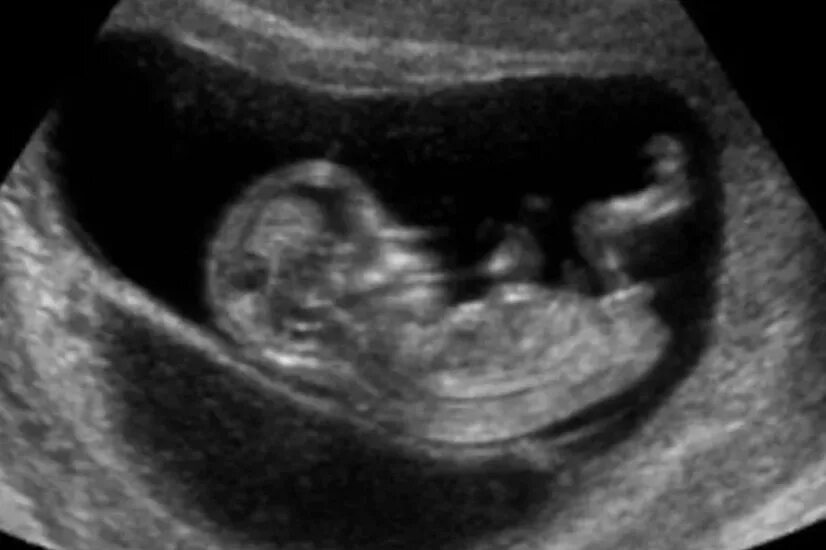

Два в триместре